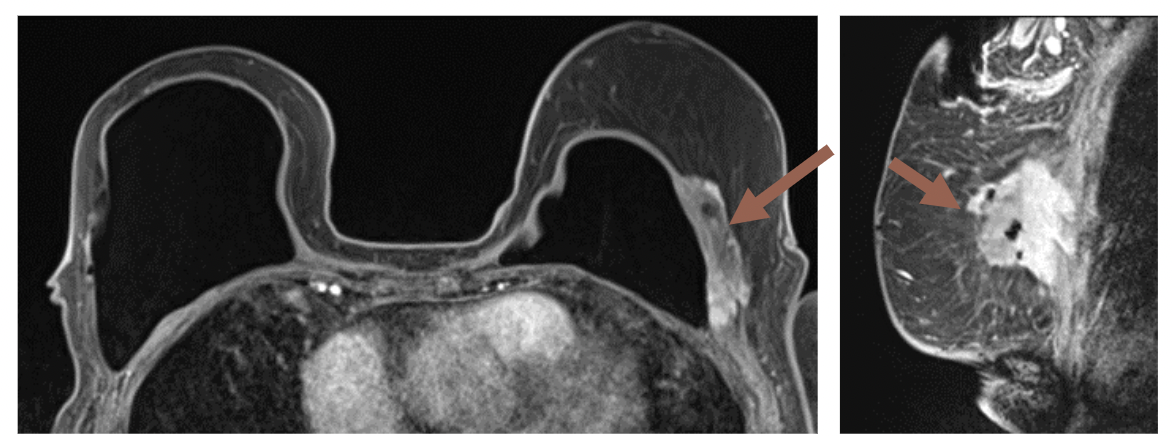

Given the increasing prevalence of breast reconstruction, researchers discussed key signs of common complications on magnetic resonance imaging (MRI), ultrasound and other imaging during a recent presentation at the American Roentgen Ray Society (ARRS) 2023 Annual Meeting in Honolulu, Hawaii.